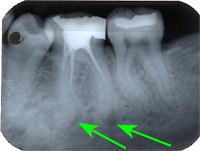

Ein 32 Jahre alter Mann kommt im November 1984 mit Zahnweh am unteren linken, zweithintersten Molaren (Backenzahn) in die Praxis. Das Röntgenbild von Abb. 1 zeigt insuffiziente Wurzelfüllungen bei allen drei Wurzelkanälen und an den Wurzelspitzen sogenannte Granulome, sichtbar als schwarze Flecken (grüne Pfeile in Abb. 1).